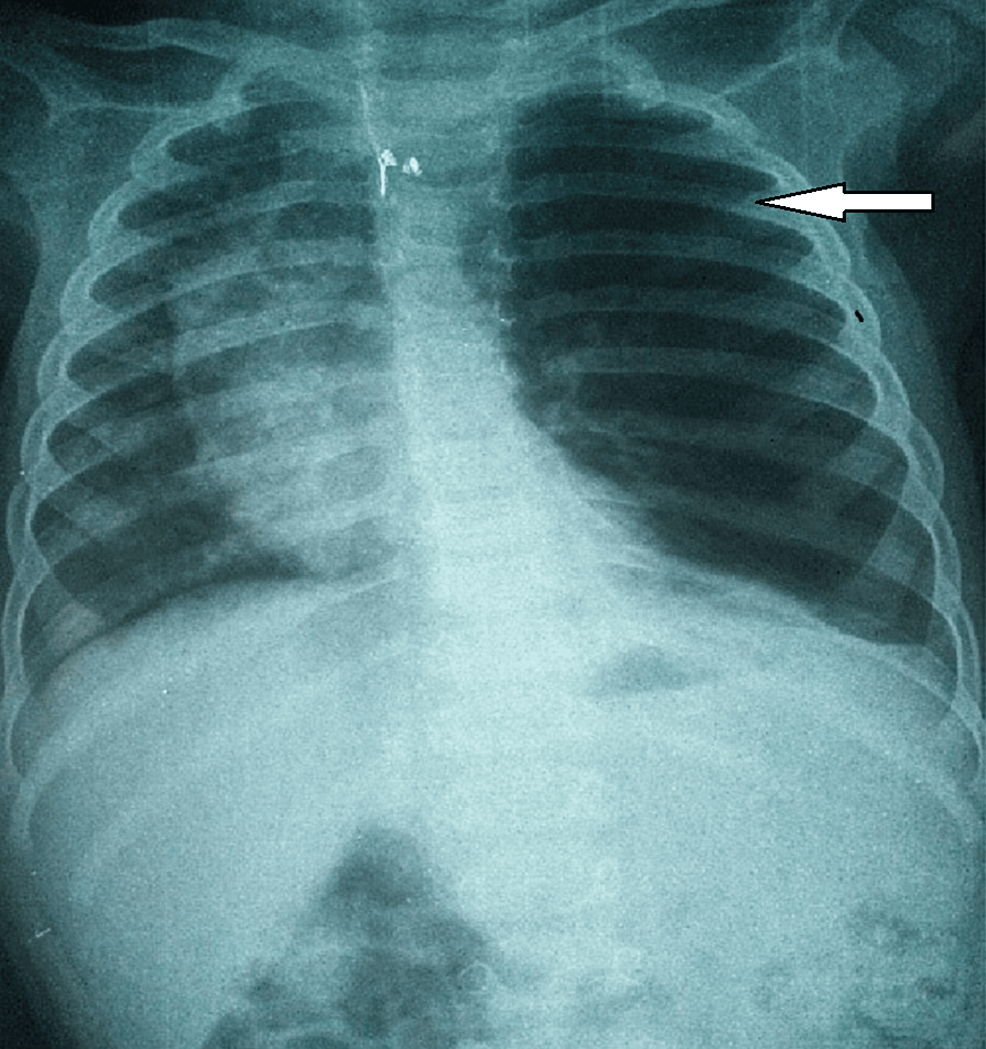

From www.researchgate.net

Chest XRay of a child with CLE. CLE, congenital lobar emphysema Congenital Lobar Emphysema Chest X Ray congenital lobar emphysema (cle), also known as congenital alveolar overdistension, is a developmental. congenital lobar emphysema is a rare lung malformation, with an estimated incidence of one case per 20. Radiolucent expanded right lung in a newborn, compatible with congenital lobar emphysema (rml & rul). congenital lobar emphysema (cle). the hrct findings were characteristic of congenital. Congenital Lobar Emphysema Chest X Ray.

Congenital lobar emphysema (CLE). Chest radiograph of a 4monthold boy Congenital Lobar Emphysema Chest X Ray congenital lobar emphysema is a rare lung malformation, with an estimated incidence of one case per 20. the hrct findings were characteristic of congenital lobar emphysema (cle). Radiolucent expanded right lung in a newborn, compatible with congenital lobar emphysema (rml & rul). congenital lobar emphysema (cle). congenital lobar emphysema (cle), also known as congenital alveolar overdistension,. Congenital Lobar Emphysema Chest X Ray.